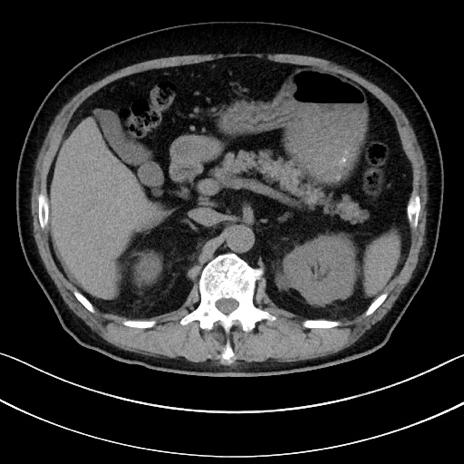

冠状断像

【症例】70歳代男性

【主訴】腹痛

【現病歴】今朝から腹痛あり。全体的に痛い。特に左上の方。排ガスが今日はない。冷や汗が出る。

【既往歴】直腸癌術後

【身体所見】左側腹部〜上腹部に圧痛あり。腹膜刺激症状明らかなではない。軽度反跳痛。左下腹部に術後瘢痕あり。

【データ】WBC 7700、CRP 0.02